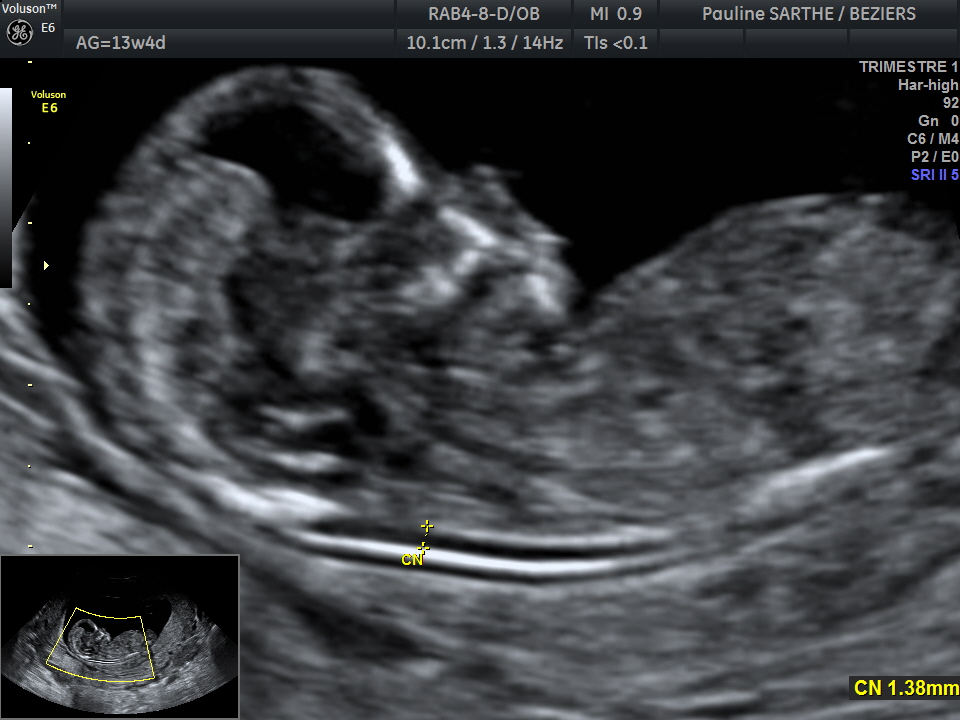

- l'échographie du premier trimestre , réalisée entre 11 et 13 semaines d'aménorrhées et 6 jours, permet de confirmer la date de début de grossesse et donc de votre accouchement, le nombre de foetus et d'effectuer un premier bilan morphologique. Vous pourrez voir votre bébé bouger et entendre son coeur : c'est un moment très émouvant!

L'examen comprendra enfin une mesure très précise sur le fœtus de profil, de la clarté nucale. Celle-ci, associée avec les prélèvements sanguins recommandés mais non obligatoires (Ht 21, PAPP-A) permettra au laboratoire de vous proposer un risque compte tenu de votre âge, pour le dépistage des trisomies 21,13 et 18.